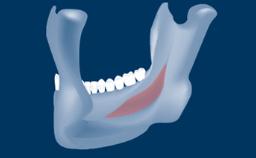

Digitally Guided Sinus Floor Elevation

In this short microlearning module on digitally guided sinus floor elevation, we delve into a specialized aspect of the digital workflow for implant-guided surgery, focusing on the use of digital guides in the sinus floor elevation technique.

• describe the indications for digital guides in SFE